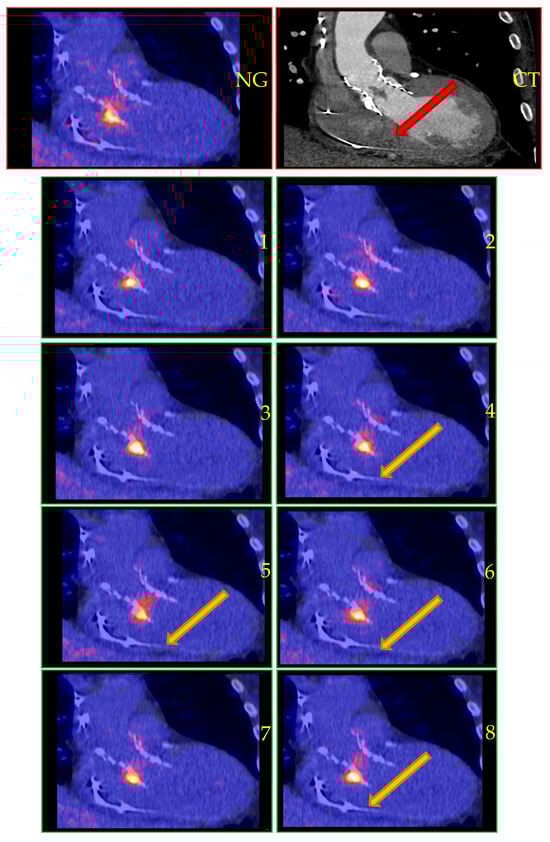

| PET results | Non-gated: IE confirmed Gated: Not available CardioFreezeTM: IE confirmed (fl+) | Non-gated: No IE Gated: No IE CardioFreezeTM: No IE | Non-gated: IE confirmed Gated: IE confirmed (fl+) CardioFreezeTM: Not available | Non-gated: Equivocal Gated: Equivocal CardioFreezeTM: Not available | Non-gated: No IE Gated: Not available CardioFreezeTM: IE confirmed | Non-gated: No IE Gated: Not available CardioFreezeTM: No IE | Non-gated: IE confirmed Gated: IE confirmed (fl+) CardioFreezeTM: IE confirmed (fl+) |